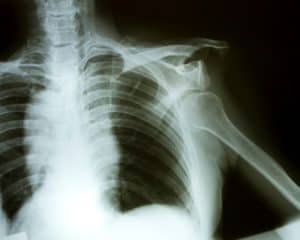

You will likely have one or several imaging tests done to determine the extent and type of shoulder injury you’ve sustained. If you do, in fact, have a dislocated shoulder, you will need the joint to be set and then immobilized to give all the soft tissue a chance to heal. This procedure can be quite painful, so medication may be given to make it more comfortable. You may also need additional imaging tests done after the joint is reset to determine if any damage was done to the soft tissue around the shoulder. If that’s the case, your doctor may suggest having surgery to repair the injured tissues.